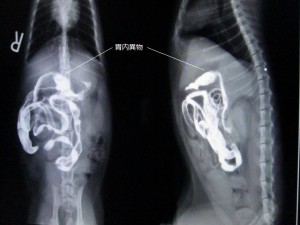

何回も吐いているとのことで来院。拾い食いのクセがあるらしく、バリウム検査を行った。

バリウム投与2時間後のレントゲンです。

ちょっと見えにくいですが、胃内に異物があります。